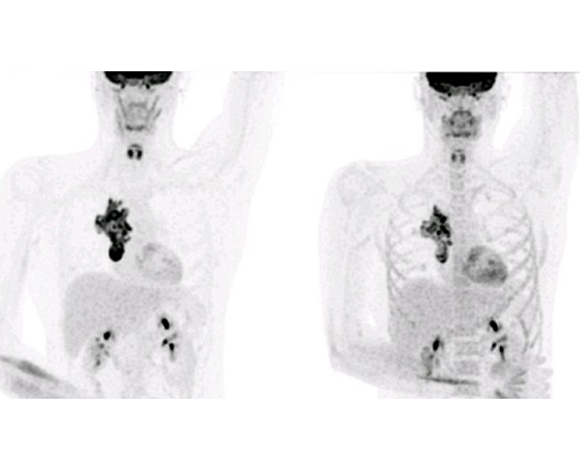

وخلال أبحاثهم، اكتشفا عيادة في أمريكا تقدّم تجارب سريرية وتمكنا من جمع 30،000$ كي يذهبوا إلى هناك. أما الآن، فلقد قيل له أنه شفي من مرضه بعد هذا العلاج الذي تضمن مزيج بين الأدوية وزراعة خلايا جذعية من أخته.

وقال السيد Eastwood أن ذهابه إلى أمريكا كان مخاطرة كبيرة وذلك لأنه لو لم يستجب إلى العلاج لكان قضى لحظاته الأخيرة في مشفى في بلدٍ آخر. ولكن بعد أخذ الخلايا الجذعية من أخته، ذهل الأطباء من النتيجة بعد أن أظهرت الفحوصات أنه قد شفي وأن الورم أخذ يختفي شيئًا فشيءٍ.